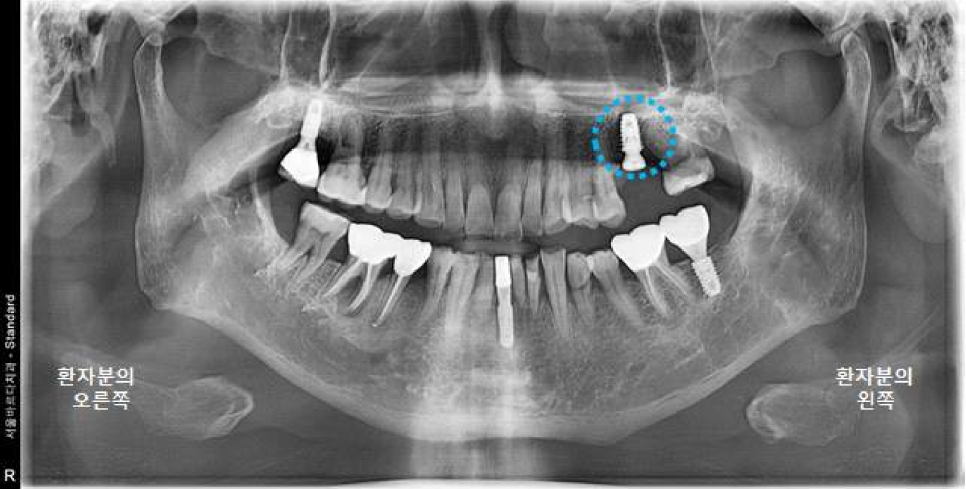

체크를 하기 위해서 파노라마 엑스레이랑

3차원 CT사진 촬영을 진행했습니다.

엑스레이상으로도 눈으로 봤을 때도 치유가 잘 되고 좋은 상태였습니다.

완료된 파노라마 엑스레이 사진입니다!

왼쪽 오른쪽 교합도 잘 맞으니 부드러운 음식부터 식사 잘 시작해보시고,

불편사항 생기시면 미리 전화 주시고 내원하시기로 하셨습니다.